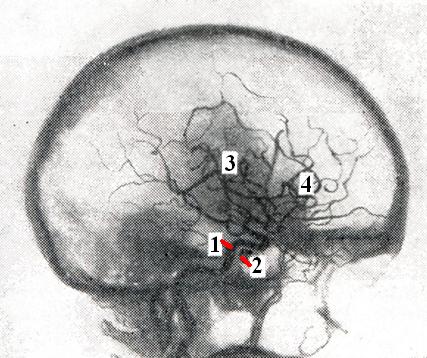

Внутрисосудистая операция (Ф. А. Сербиненко, 1971) заключается в следующем. Через пункциониую иглу с просветом 1,3 мм, которой пунктируют сонную артерию, в кавернозный отдел сонной артерии вводят баллон из латекса. Баллон раздувают рентгеноконтрастным веществом до тех пор, пока он не выключит соустье и сонную артерию из кровообращения. Затем баллон обтурируется твердеющим полимером и сбрасывается с катетера.

С помощью баллона окклюзируется полость кавернозного синуса, и таким образом может быть выполнена реконструкция кавернозного отдела сонной артерии (рис. 2).